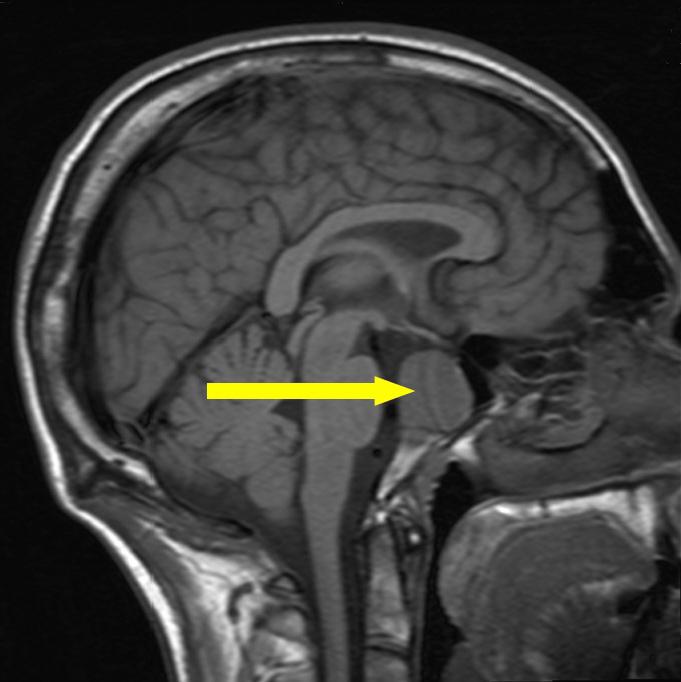

Микроаденома — опухоль доброкачественного характера, которая состоит из железистых клеток гипофиза. Маленькие размеры новообразования и отсутствие симптомов во многих случаях затрудняют раннее выявление и диагностику заболевания. Чаще всего подобные новообразования обнаруживаются случайно, при обращении пациента к врачу по поводу других заболеваний. Очень часто врач невропатолог назначает компьютерную или магнитно — резонансную томографию головного мозга. А бывает и сам пациент по каким-то причинам решает пройти подобное исследование.

Диагностирование микроаденомы